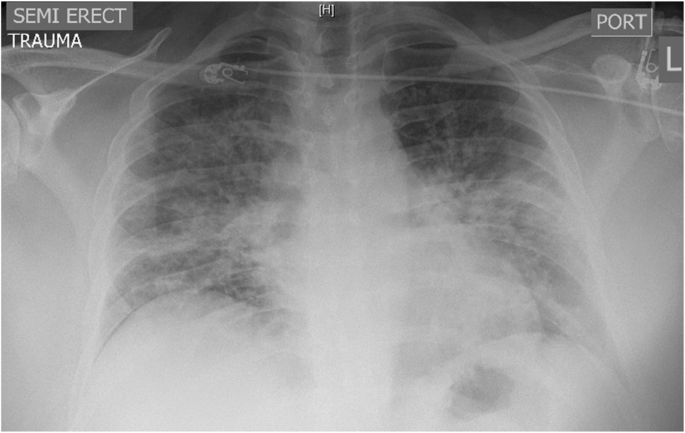

Although abnormalities are frequently found on chest imaging, the findings are non-specific and variable. In the Illinois/Wisconsin cohort, 83% were found to have abnormalities on chest radiograph and 100% were found to have abnormalities on Computed Tomography (CT) of the chest [15]. A chest x-ray should be obtained in patients with e-cigarettes use who present with respiratory, GI, or constitutional symptoms. Typical of findings on chest radiograph of EVALI is diffuse hazy bilateral opacities with occasional subpleural sparing (Fig. 1). Involvement of all lung lobes can be seen, but is not universal. Additionally, increased interstitial markings can be seen characterized by Kerley B lines. A CT chest should be pursued if there is high suspicion for EVALI but the chest radiograph is normal given the improved sensitivity of CT and/or to assist in ruling out other etiologies. While imaging findings are variable in EVALI, typical findings on chest CT are bilateral ground glass opacities (Fig. 2). Additionally, upper lobe predominant centrilobular nodules are often seen on chest CT [44]. Since findings on chest imaging are non-specific, other etiologies of lung injury should be considered.